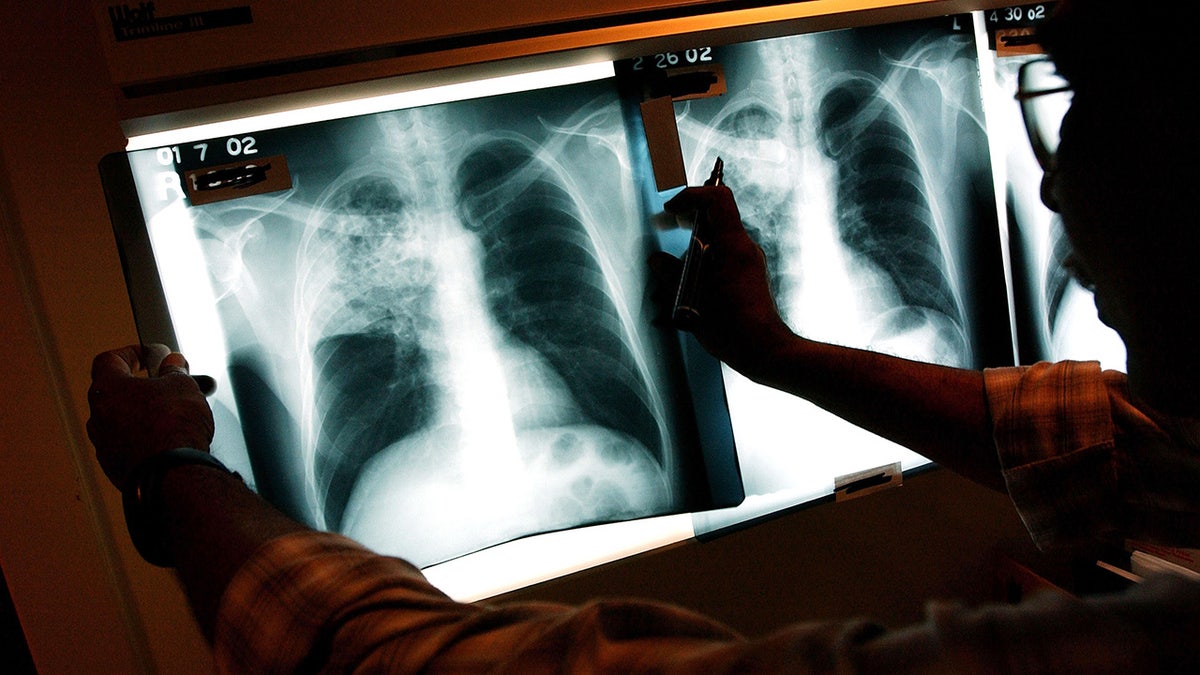

The x-ray of a TB patient in New York in 2002. (Spencer Platt/Getty Images)